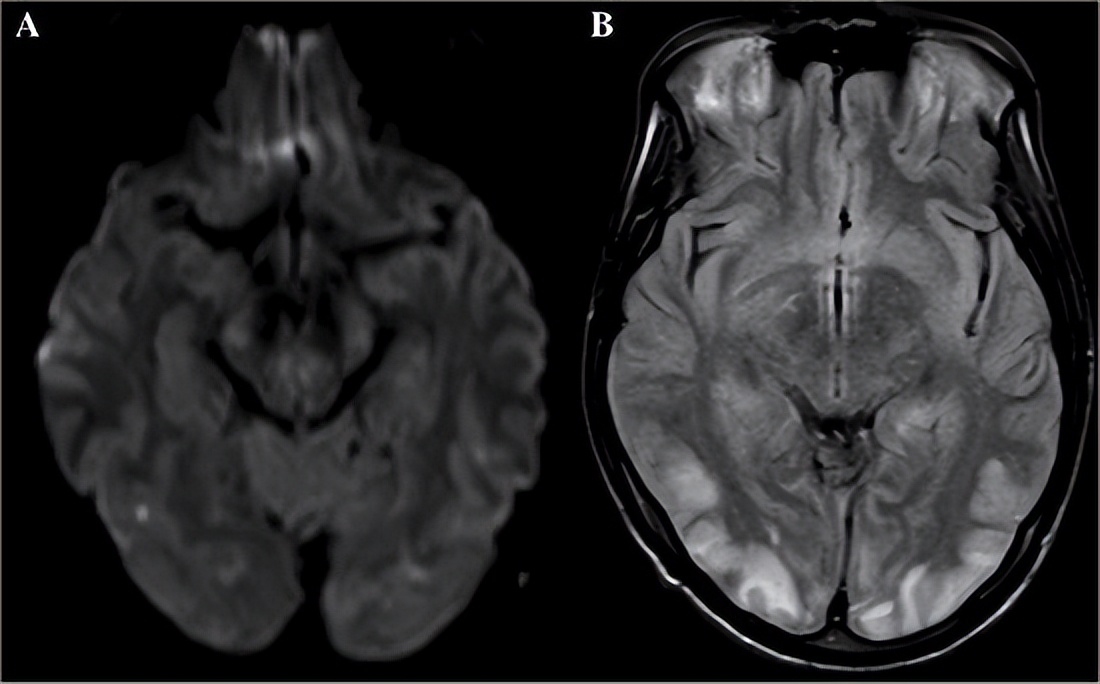

常见原因之三:中风 中风即“脑卒中”,是一种脑血管异常引发的脑部损伤,可分为脑出血和脑梗死两种类型,二者均可引发局部缺血和坏死。脑是神经系统的“司令部”,脑部病变可引发任何身体异常,包括手部的感觉和运动功能异常。1、症状特点。一般情况下,手部的感觉和运动功能异常只是诸多中风症状的一部分,相关的症状可能还包括瘫痪、思维和意识异常、语言功能异常、行走功能异常、整个上肢功能异常等。在极为巧合的情况下,也可能仅仅出现手部症状,但一般不会像腕管综合征那样仅仅引发桡侧三指半的症状。当然,中风的精确诊断还是要依靠精密的脑部影像。